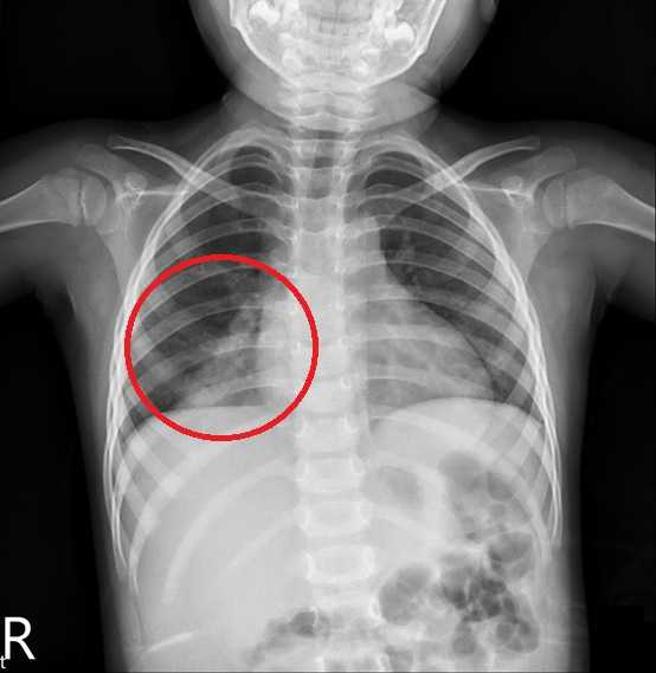

不只是医院加护病房,社区中可能也有抗药性细菌风险。林口长庚医院儿童感染科邱政洵曾指出,一名12岁男童因右臀部疼痛和间歇性发烧4天赴急诊就医,检查发现感染多重抗药性金黄色葡萄球菌,此菌不仅造成男童肺栓塞,还合併化脓性髋关节脓肿,经长达1个月的药物治疗及手术治疗,才得以出院回家。

据疾管署资料,台湾今年的肺炎霉浆菌病例数高于过去3年,其中近7成患者都是儿童,会有发烧、咳嗽、呼吸急促等症状。(图/报系资料照)